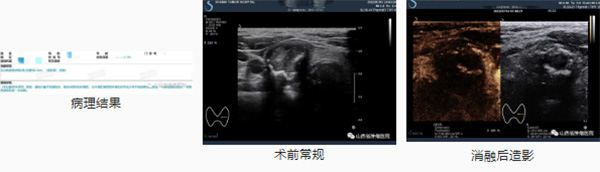

一例女性甲状腺左叶结节2.05*1.89*3.07cm的结节性甲状腺肿,消融时间4分钟;另一例男性甲状腺右叶结节0.71*0.43*0.39cm的微小乳头状癌,消融时间1分钟,术后病人安全返回病房。次日复查超声检查,无异症,安排患者出院。

微小乳头状癌:

超声引导下微波消融治疗可以作为部分甲状腺良性结节、甲状腺微小癌患者外科手术之外的有效手段。其作为一种微创治疗方法,与传统的手术相比,具有微创、安全、对正常组织损伤小、无瘢痕残留的优势。病人无需开刀,在局部麻醉后,利用超声引导,将消融针经皮肤穿刺进入肿瘤中,利用热效应将肿瘤消融灭活,达到原位灭活。